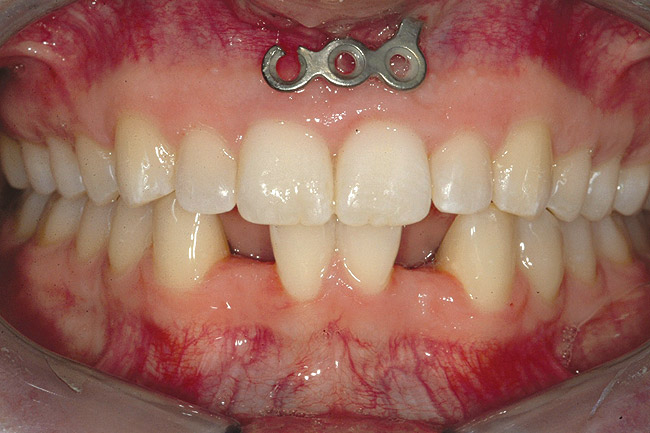

Fig 6 (and Fig 7). Prerestorative orthodontics was completed in 5 months. Final result 3 years, 4 months after completion.

Figure 6

Fig 7 (and Fig 6). Prerestorative orthodontics was completed in 5 months. Final result 3 years, 4 months after completion.

Figure 7

Fig 8 (and Fig 9). Teeth Nos. 5 and 12 were converted to Nos. 6 and 11, and Nos. 6 and 11 were converted to Nos. 7 and 10. Nos. 4 and 13 were enlarged. Note stability and absence of orthodontic relapse. Before-and-after smiles. Periodontist: Edward P. Allen, DDS, PhD. Prosthodontist: Robert R. Winter, DDS.

Fig 9 (and Fig 8). Teeth Nos. 5 and 12 were converted to Nos. 6 and 11, and Nos. 6 and 11 were converted to Nos. 7 and 10. Nos. 4 and 13 were enlarged. Note stability and absence of orthodontic relapse. Before-and-after smiles. Periodontist: Edward P. Allen, DDS, PhD. Prosthodontist: Robert R. Winter, DDS.